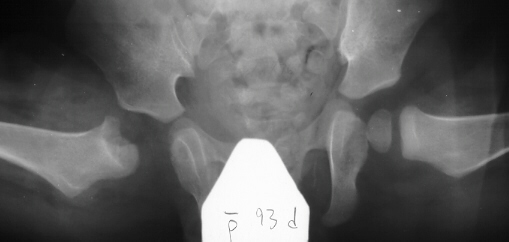

- Hospital Day 6: Respiked to 103.4. R hip Xray showed a defect in proximal

medial metaphysis, Possible osteomyelitis. The child was than taken to

the operating room for Incision & Drainage of Right hip via anterolateral

approach with suction irrigation system (seropurulent fluid drained).

- Post Operative Day 7: Drains removed. Respiked to 101.6. R hip Xray:

suggestion of demineralization of proximal metaphysis. The hip was reaspirated

and pus was obtained. Cultures neg.

- Post Operative Day 12: Respiked to 103.6. Gentamicin 1 mg IV q6 added

to Nafcillin. Daily aspirations of 10 cc purulent fluid, all cultures neg.

- Post Operative Day 18: R hip Xray: subluxation of R hip, possible metaphyseal

lucency consistent with osteomyelitis. Taken to OR for repeat I & D

of R hip via posterior approach with Penrose drains and hip spica cast

(15cc seropurulent fluid drained). Antibiotics changed to Oxacillin 225mg

IV q4.

Institute. Initial labs: WBC 15,100, ESR 72. R hip Xray: changes in proximal

. metaphysis including lucency and demineralization, hip subluxated. Treated

with oxacillin and Pavlik harness.

- 2 month Office Follow Up: Rt hip Xray: progressive destruction of capital

femoral epiphysis, cystic changes in metaphysis consistent with AVN.